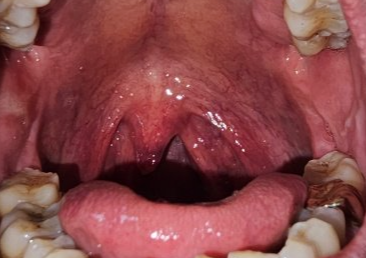

몸의 컨디션에 떨어져 있을 때, 또는 음주를 과도하게 한 다음날 목젖이 부어있고 염증이 생겨있는 것을 볼 수 있습니다. 정상적인 목젖에 비해 붓기가 심하고 늘어져 있는 현상이 나타나고 통증도 함께 동반되는 경우가 있습니다. 다른 말로 목젖염 이라고도 부르는 이 질환의 발생 원인 및 치료방법에 대해서 알아보겠습니다.

우리가 입을 벌리면 안쪽 끝에 작게 메달려 있는 부위가 있는데 흔히 목젖이라고 부릅니다. 연조직으로 되어 있어 부드럽고 신축성이 있는 형태로 되어 있으며 감염 및 염증에 취약한 특징이 있어 몸의 컨디션이 떨어져 있을 때 먼저 이상 현상이 생길 수 있습니다.

대표적인 증상으로 목젖이 평소보다 많이 붓고 모양의 변형이 일어날수 있습니다. 증상이 심한 경우는 목젖 늘어짐 현상 때문에 음식물을 섭취하거나 말을 할 때도 불편함을 초래하게 됩니다. 염증 발생 수준이 높을 때는 목젖 주변에 고름이 차는 현상이 발생되기도 하는데 자연치유보다는 병원 약 처방(항생제)을 받아 치료를 받는 것이 빠르게 증세를 호전시키는 방법이 됩니다.